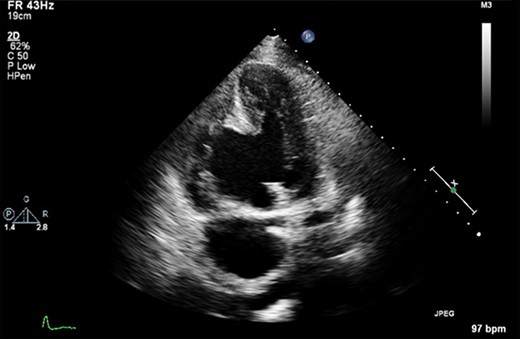

Cardiac MRI described a large aneurysm involving the basal and mid-inferoseptum and extending into the basal and mid-inferior walls (Fig. 2). There was full thickness infarction of the aneurysmal wall and an associated complex VSD with significant left to right flow (Qp:Qs 2.8:1). Coronary angiogram showed a mild circumflex disease and a significant disease of the left anterior descending (LAD) and right coronary artery (RCA) (Fig. 3).

Cardiac MRI demonstrating a LV aneurysm leading to abnormal dilatation of the mitral annulus.